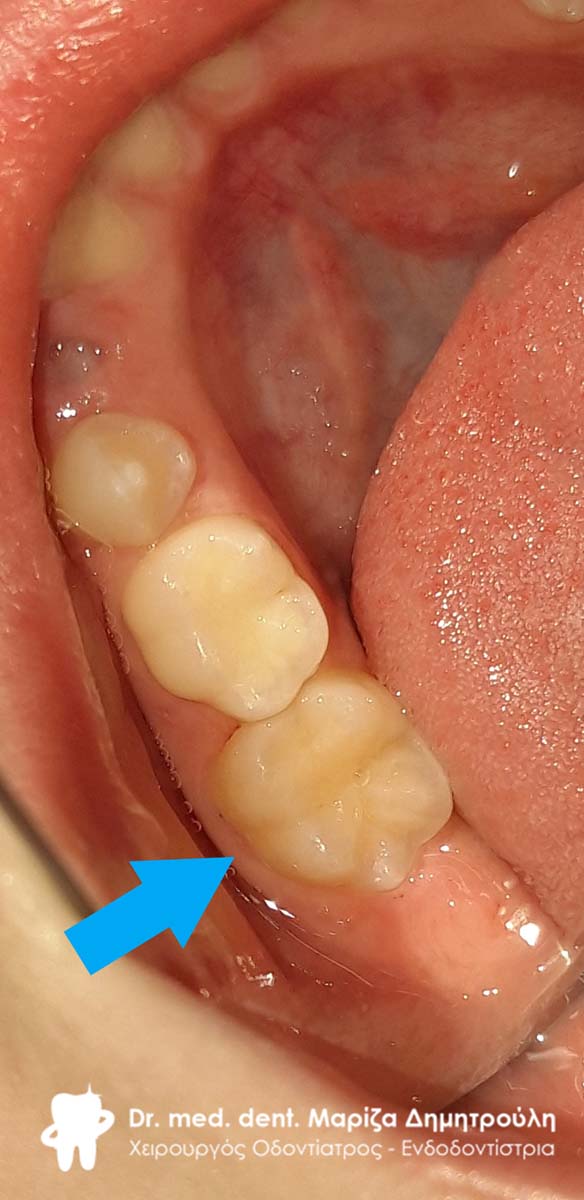

Στα πλαίσια του ετήσιου προληπτικού οδοντιατρικού ελέγχου πραγματοποιήθηκε στο μικρό ασθενή προληπτική κάλυψη οπών και σχισμών (sealant) στον πρώτο αριστερό μόνιμο γομφίο της κάτω γνάθου.

ΠΡΙΝ

ΜΕΤΑ